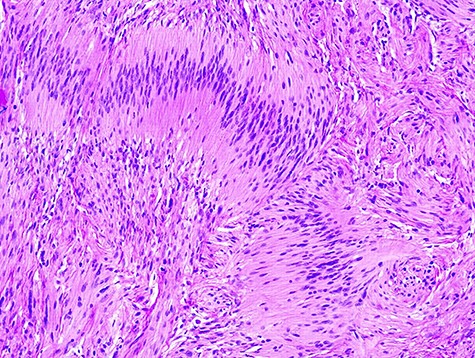

Histological examination of the operating material revealed a tumor formed by spindle Schwann cells (S100+), exhibiting hypo and hyper cellular areas. There were no mitosis figures or necrosis (Fig. 4), compatible with nerve sheath neoplasia.

Typical spindle cells of schwannoma with hipo and hyper cellular areas.